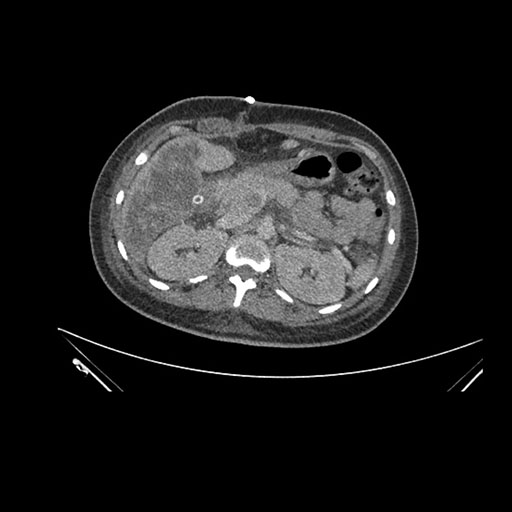

Axial Arterial

Axial Venous

Imaging analysis

Based on initial findings, which issue(s) would you be most concerned about?